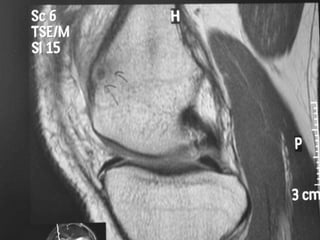

Osteoid Osteoma - MRI

• MRI has not been useful in the diagnosis of

osteoid osteoma.

• MRI is reserved for equivocal cases because it

can suggest the diagnosis of osteoid osteoma.

• MRI interpretation may result in errors in

diagnosis, most often confusion with

malignancies.

Osteoid Osteoma -MRI • MRI has not been useful in the diagnosis of osteoid osteoma. • MRI is reserved for equivocal cases because it can suggest the diagnosis of osteoid osteoma. • MRI interpretation may result in errors in diagnosis, most often confusion with malignancies.